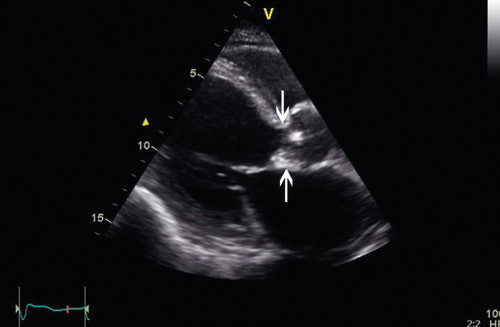

På bakgrunn av akutt hjertesvikt og nyoppstått hjertebilyd fant vakthavende lege indikasjon for ekkokardiografi, som ble utført allerede få timer etter innleggelsen. Venstre ventrikkel var dilatert, med endediastolisk dimensjon på 6,7 cm og endesystolisk dimensjon på 4,7 cm. Ejeksjonsfraksjonen ble estimert til 48 % (nedre normalområde). Slagvolumet var 93 ml, og med en hjertefrekvens på 105 slag/min ble minuttvolumet da 9,75 l/min. Aortaklaffen var trikuspid, med en endokardittsuspekt pendulerende vegetasjon på den ikke-koronare klaffen, 0,7 cm x 0,9 cm, og en nesten like stor vegetasjon på den høyre koronare klaffen (fig 1, videosnutt 1, videosnutt 2). Det var ingen tegn til abscessdanning. Den ikke-koronare klaffen var nesten totalt destruert, og dette ga opphav til stor aortainsuffisiens, med trykkhalveringstid på 56 ms (fig 2, videosnutt 3, videosnutt 4). Høyre ventrikkel var normal, med en liten trikuspidal insuffisiens. Trikuspidallekkasjegradienten var 47 mm Hg, og v. cava målte 1,7 cm, med noe redusert respiratorisk variasjon. Dette indikerte betydelig grad av pulmonal hypertensjon, med et estimert trykk i det lille kretsløp på om lag 60 mm Hg. Det ble også påvist en liten til middels mitralinsuffisiens.